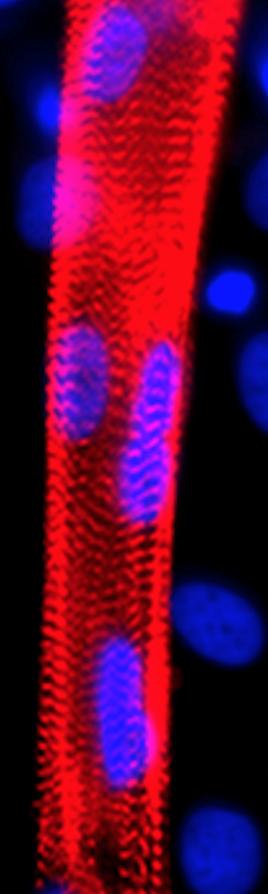

Muscle fibers form when cells known as myoblasts, containing a single nucleus, mature and fuse together to form myotubes with multiple nuclei, which further mature into muscle fibers that contract. "The fusion of myoblasts into myotubes is one of the most distinctive features of skeletal muscle," says Lee, an assistant professor of neurology at the Johns Hopkins University School of Medicine. "What we can now do is make fusion-capable myoblasts, which are easy to grow and therefore make it easier to study how diseases like DMD interfere with the fusion process."

To confirm its finding, the research team applied its "recipe" to induced pluripotent stem (iPS) cells generated from the skin cells of a dozen healthy donors and from five patients with DMD, each with a different genetic variation. With both healthy iPS cells and DMD iPS cells, the scientists were able to create myoblasts that could generate myotubes, though the DMD-derived cells were 10 times less efficient at fusing and couldn't contract.